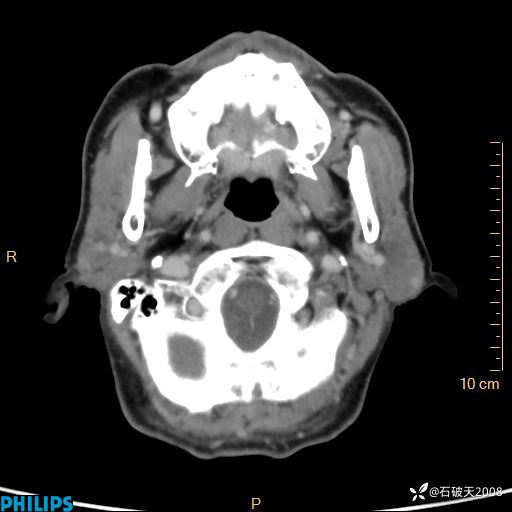

动脉期